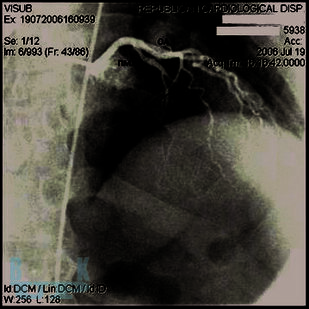

В пособии представлены особенности клиники и диагностики врождённой коронарной патологии – мышечного мостика, наличие которого при определённых условиях может стать причиной острого коронарного синдрома и внезапной сердечной смерти (на втором месте после гипертрофической кардиомиопатии) у молодых людей без факторов риска ишемической болезни сердца. Последовательно изложены возможности повышения информативности функциональной пробы с физической нагрузкой и стресс-эхокардиографии в выявлении ишемии миокарда, вызываемой коронарной аномалией. Далее показана эффективность медикаментозных средств, чрескожного вмешательства, хирургической коррекции у больных с мышечными мостиками.